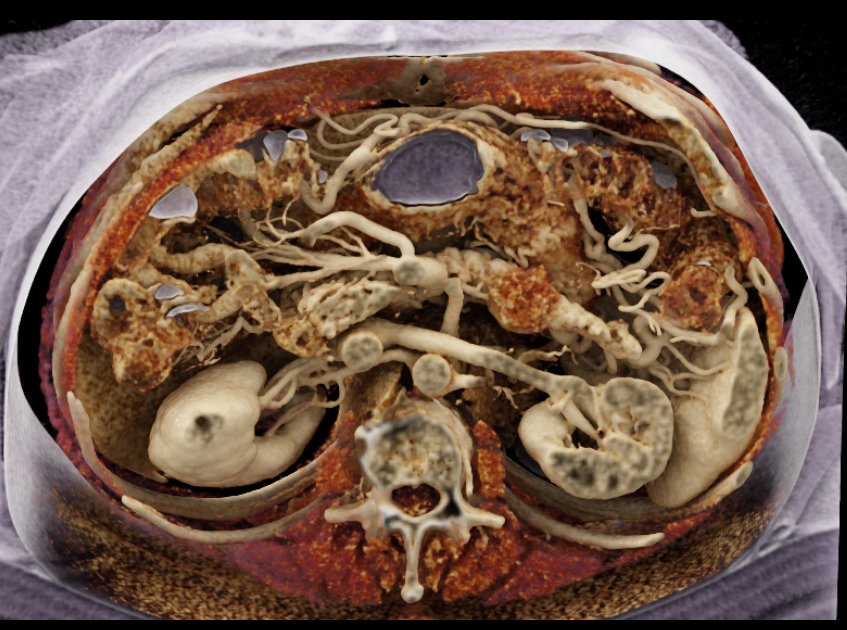

Carcinoma Tail of Pancreas